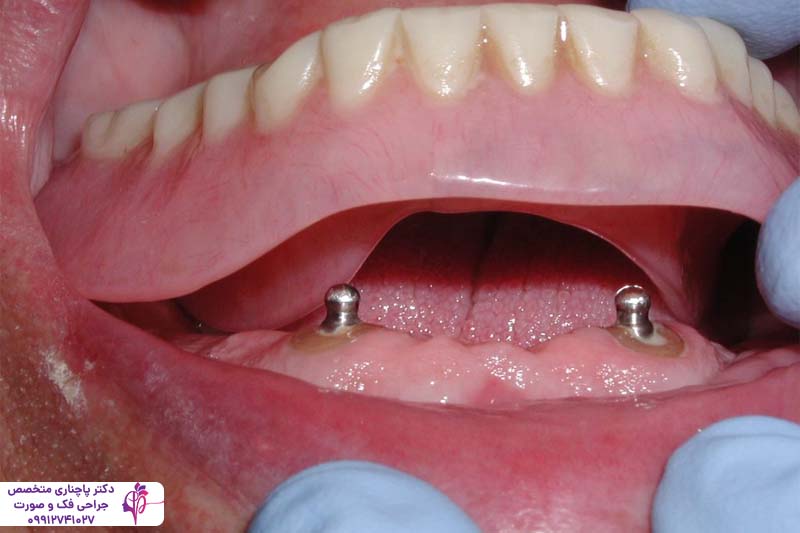

قبل از اینکه درباره اوردنچر اقساطی در تهران صحبت کنیم به یک توضیح کوتاه درباره ماهیت اوردنچر دندان میپردازیم. اوردنچر نوعی پروتز دندانی است که روی پایههای ایمپلنت که از قبل داخل استخوان فک قرار گرفتهاند نصب میشود در بعضی موارد این پروتز را میتوان به کمک گیرههای مخصوص روی دندانهای سالم باقیمانده هم نصب کرد. بنابراین این پروتز بر خلاف دندان مصنوعی سنتی هیچ تماسی با لثه دندان ندارد و به همین دلیل هم ثبات بیشتری دارد و هم باعث التهاب و تحلیل رفتن لثه نمیشود. در نتیجه این ثبات پروتز موقع حرف زدن یا غذا خوردن حرکت نمیکند و جابجا نمیشود و عملکردی شبیه به دندان طبیعی دارد.

ساختار کلی اوردنچر شامل یک سری دندان مصنوعی از جنس آکریلیک است که به واسطه اتصالات فلزی مخصوص به ایمپلنتها یا دندانهای طبیعی متصل میشود. همین اتصالات محکم باعث شده این پروتز بتواند نیرو و فشار جویدن را بیشتر تحمل کند. این فشار به پایهها منتقل میشود و فشار کمتری به بافتهای نرم لثه وارد میکند.